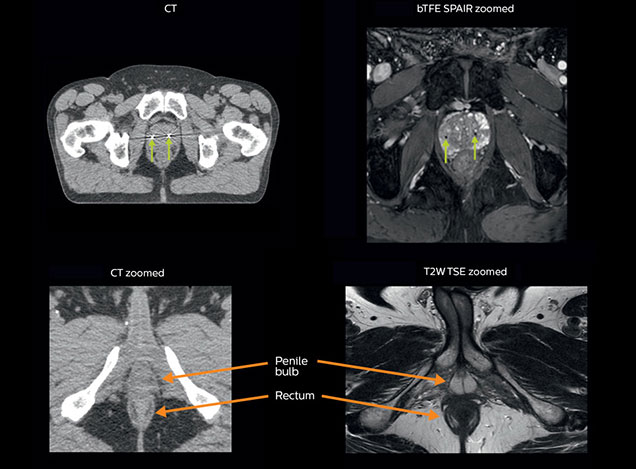

MRI is capable of visualizing the prostate and the surrounding organs such as rectum, penile bulb, bladder, the apex and seminal vesicles, as well as visualizing intra-prostatic lesions [2,4].

“All our patients undergo an MRI exam – along with CT – before radiotherapy of the prostate,” says Dr. Philippens. “For prostate delineation, we are scanning a balanced TFE with fat suppression. We can also see the gold fiducial markers in these images, which are used for position verification and are therefore used for registration to CT. For geometric accuracy of the image, we choose a 3D sequence, which is corrected for the gradient non-linearities in all directions.

A 63-year-old patient with prostate cancer, cT3bNxM, Gleason 7, underwent MRI on Ingenia 3.0T MR-RT before radiation therapy.

Intraprostatic lesions are visible on the bTFE MR image, but not on the CT image. MRI shows excellent soft-tissue contrast for the visualization of critical structures like the rectum and penile bulb.

Fiducial markers (green arrows) are used in registration of MR images to CT, to transfer the MR-based delineations onto the CT image dataset.